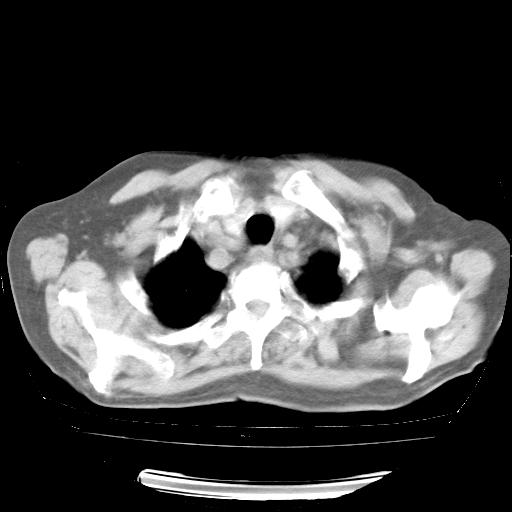

今天部分检查

轻微咳嗽,无痰,(体温正常时)R20次/分,P75次/分,双肺底、腋下可闻及少量捻发音。下肢轻度浮肿。

血常规:白细胞9.11×109/L,N0.92,L5.64,血小板39.2×109/L,HB148g/L,ESR2mm/H。

尿常规:潜血+

血生化:总蛋白69.71g/L,白蛋白38.40g/L,球蛋白31.31g/L,CRP27.9mg/L,尿素氮11.98mmol/L,肌酐106μmol/L,乳酸脱氢酶1099 U/L,肌酸激酶108U/L,CK-MB 61U/L。

腹部B超:胆囊壁增厚,肝、胆、胰、脾、肾无异常,肠系膜淋巴结、腹膜后淋巴结无增大。

ECG:右心室增大

心脏超声检查:无右心室增大。

增加治疗:异烟肼、利福平、乙胺丁醇,静滴左氧氟沙星、参麦注射液。甲强龙从80mg暂减为40mg。

强的松3月1日改为10mg qd,4月1日改为10mg qod。3月份以前的减量过程和环磷酰胺疗程需等明天查看记录(我岳父自己做的记录在他家里)。